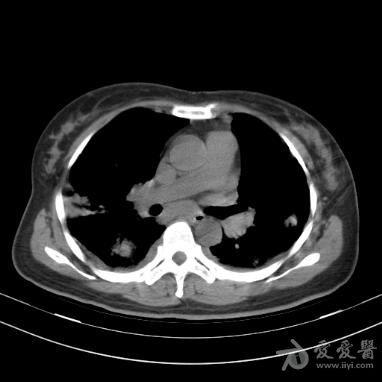

左肺斑片实质影 [病例帖]

上图所示,病变位于右上肺,有斑片状影,周围夹杂着条索影哪改变.

胸部ct提示双肺多发支气管囊状,柱状扩张,以及散在斑片影

h1n1流感,双肺上叶多发斑片状磨玻璃影 f/39 h1n1